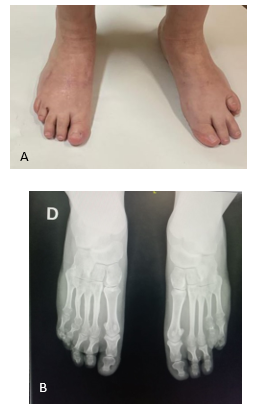

CASO 2: Paciente de sexo femenino, 23 años, presenta un acortamiento congénito del cuarto metatarsiano, bilateral y simétrico, acompañado de un acortamiento del cuarto metacarpiano de ambas manos. No presenta familiares de primer ni segundo grado con dichas alteraciones. Consulta por problemas estéticos del pie, dolor en la bipedestación y una metatarsalgia de trasferencia de los metatarsianos centrales, con hiperqueratosis en planta a dicho nivel. El cuarto dedo estaba subluxado, flexible, sin lesiones en dorso, no siendo doloroso a la palpación. No presentaba compromiso vásculo-nervioso distal. La alineación del retropié era neutra y los pulsos distales estaban presentes. Las articulaciones tibiotarsiana y subastragalinas eran móviles, indoloras y simétricas. El resto del examen físico era normal. Se clasifica según Lamm en 4 AC. 3 (Figura 7)

Figura 7 A y B: Presentación clínica de la paciente. Se observa la braquimetatarsia del cuarto radio, un segundo y tercer dedos largos.

En la radiografía se observa un cuarto metatarsiano hipoplásico bilateral, generando una interrupción clara de la parábola metatarsal; asocia un segundo y tercer metatarsiano largo y un primer metatarso corto. (Figura 8) El metatarsiano hipoplásico no es curvo y no presenta alteraciones en la epífisis distal. Hay una subluxación de la articulación metatarsofalángica.

Figura 8: Radiografía preoperatorio. Se observa alteración de la parábola metatarsal, braquimetatarsia que afecta al cuarto metatarsiano, segundo y tercer metatarsianos largos y subluxación de metatarso falángica.

Con un seguimiento de 4 años (Figura 12 y 13) se observan en la radiología las osteotomías consolidadas, el restablecimiento de la parábola metatarsal, congruencia articular y un buen resultado estético.

Figura 13: A: Situación clínica con 4 años de evolución. B: Radiografías con un seguimiento de 4 años de evolución.

Con 4 años de seguimiento el paciente mantiene una buena evolución score AOFAS 47/87. Sin pérdida de la reducción de metatarsofalagica, sin limitación en el calzado ni en las actividades diarias.